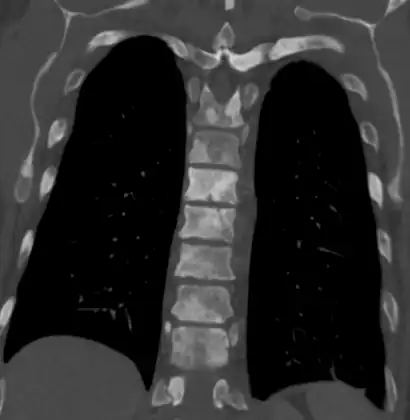

The most important distinction made by any staging system is whether the cancer is confined to the prostate. In the TNM system, clinical T1 and T2 cancers are found only in the prostate, while T3 and T4 cancers have metastasized. Several tests can be used to look for evidence of spread. Medical specialty professional organizations recommend against the use of PET scans, CT scans, or bone scans when a physician stages early prostate cancer with low risk for metastasis.[95] Those tests would be appropriate in cases such as when a CT scan evaluates spread within the pelvis, a bone scan looks for spread to the bones, and endorectal coil magnetic resonance imaging evaluates the prostatic capsule and the seminal vesicles. Bone scans should reveal osteoblastic appearance due to increased bone density in the areas of bone metastasis—the reverse of what is found in many other metastatic cancers.

In men with high-risk localised prostate cancer, staging with PSMA PET/CT may be appropriate to detect nodal or distant metastatic spread. In 2020, a randomised phase 3 trial compared Gallium-68 PSMA PET/CT to standard imaging (CT and bone scan). It reported superior accuracy of Gallium-68 PSMA-11 PET/CT (92% vs 65%), higher significant change in management (28% vs 15%), less equivocal/uncertain imaging findings (7% vs 23%) and lower radiation exposure (10 msV vs 19 mSv). The study concluded that PSMA PET/CT is a suitable replacement for conventional imaging.[96]

Sclerosis of the bones of the thoracic spine due to prostate cancer metastases (CT image)

Sclerosis of the bones of the thoracic spine due to prostate cancer metastases (CT image) Sclerosis of the bones of the thoracic spine due to prostate cancer metastases (CT image)

Sclerosis of the bones of the thoracic spine due to prostate cancer metastases (CT image) Sclerosis of the bones of the pelvis due to prostate cancer metastases

Sclerosis of the bones of the pelvis due to prostate cancer metastases